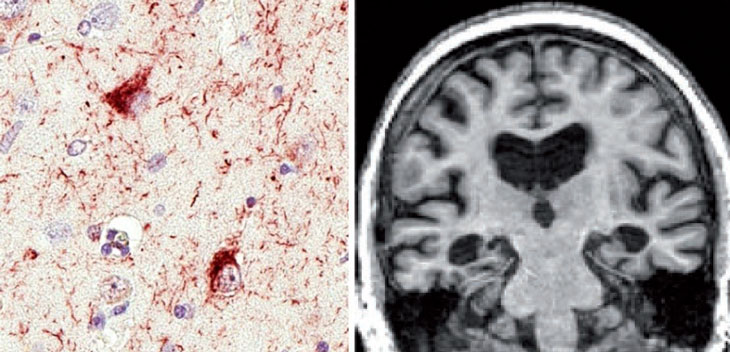

MEET “LATE” A disease now dubbed LATE causes memory trouble in elderly people, similar to what’s seen in Alzheimer’s disease, but it looks different in the brain.

LATE comes with memory trouble and dementia — symptoms that mirror Alzheimer’s, Nelson says. But instead of the plaques and tangles that mark the brains of people with Alzheimer’s disease, LATE is characterized by a lesser-known protein called TDP-43. In LATE, that protein accumulates and spreads through parts of the brain that are key to thinking and memory, including the amygdala and hippocampus.

In Brain, Nelson and his colleagues describe the signs of LATE in the brain in a series of stages, from less severe to most severe. But the trouble is that these signs, which include the spread of TDP-43 and occasionally signs of damage to the hippocampus, can be found only after a person has died.

The researchers hope that giving the disease a name and description will make it easier to spot. Take a hypothetical 80-year-old patient with memory loss who tests negative for signs of Alzheimer’s in the brain, and whose MRI shows a smaller-than-normal hippocampus. “There, I think this notion of LATE is going to start rising quickly to the top,” Greicius says. Still, he cautions that “this is a disorder that we’re beginning to get a handle on. We’re not quite sure yet.”